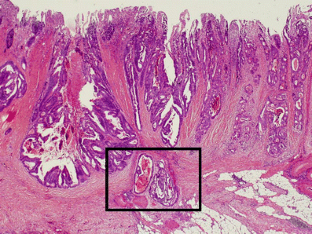

Fig. 1

Fig. 2